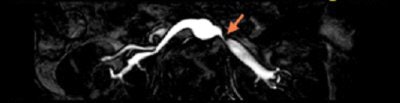

![]() |

| Above, high-resolution contrast-enhanced renal MRA with inadequate depiction of the segmental renal branches. Below, noncontrast Time-SLIP renal MRA depicting the main renal artery, as well as the segmental branches. Images courtesy of Toshiba America Medical Systems. |